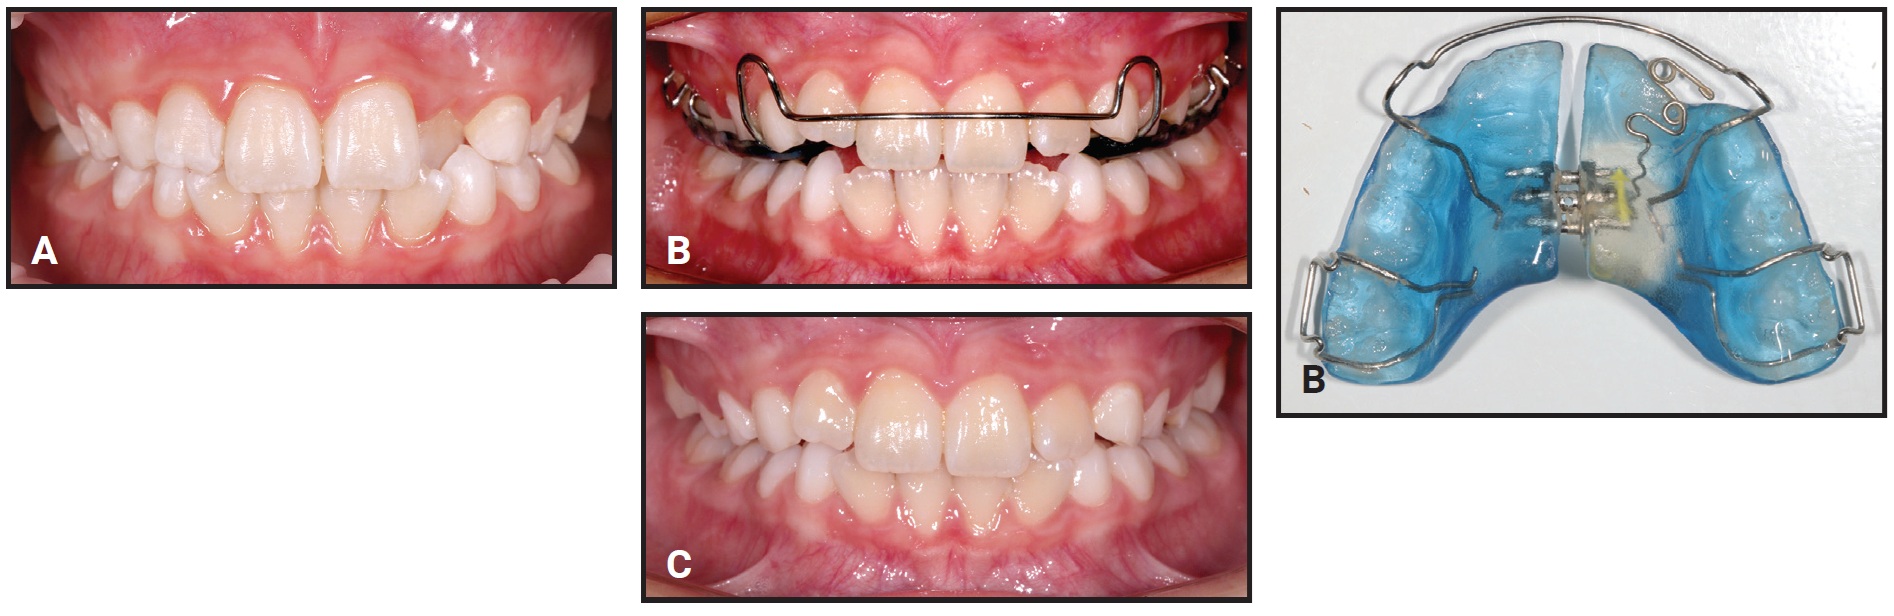

1. Can I treat this permanently? Examples are anterior and posterior crossbite correction. For nonskeletal anterior crossbite correction, a maxillary removable appliance can often be used, unless significant incisor rotational and torque control are needed (Fig. 1A and 1B).

Fig. 1 Case 1. A. 7½-year-old male patient with anterior crossbite and forward mandibular shift before treatment (continued in next image).

Fig. 1 (cont.) Case 1. B. Anterior crossbite corrected after nine months of treatment with removable maxillary appliance; mandibular incisors show spontaneous improvement in alignment.

Correction is usually accomplished in four months of full-time wear. A posterior biteplane is used when the vertical overbite exceeds 2-3mm, to allow bite opening for anterior crossbite correction; the biteplane is reduced after the crossbite is corrected to prevent deepening of the overbite. Space must be available for tooth movement to occur; therefore, maxillary expansion may sometimes be needed (Fig. 2).

Retention is not needed when the overbite is complete. Any gingival retreat on the mandibular incisors will improve after crossbite correction2 (Fig. 3). Mandibular incisor irregularity often improves secondary to maxillary incisor alignment, provided adequate space is available.